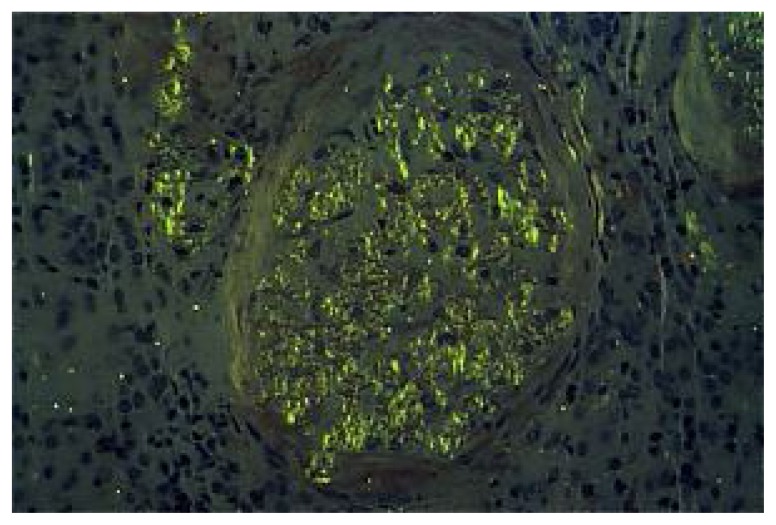

Fig 5.

Congo red stains of biopsy material showing characteristic “apple-green” birefringence of amyloid deposition.

Histopathological examination is necessary may miss the diagnosis of amyloidosis if simultaneous Immunostaining is not done. (7) On Congo red staining, the material shows the classical apple-green birefringence under polarized light.